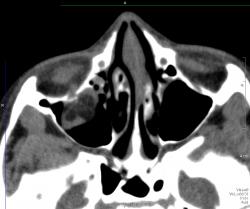

Отломок напоминает открытую дверцу, в которую вываливается нижняя прямая мышца и клетчатка. Бывает, что такая "дверца" захлопывается и ущемляет содержимое орбиты. Тут нужен зоркий глаз и знание клиники, так как сам перелом можно уже и не увидеть, отломок встал на место.

Зрение в порядке за исключением "пустяка" диплопии. Почему называется взрывным переломом? Вероятно потому, что перелом не от прямого удара по кости, иначе ломался бы край орибы. Ломается тонкое место в дне орбиты от резко повышения давления в орбите в результате прямого удара. Американцы приводят как пример типичный механизм прямого удара бейсбольным мячом. Как ни странно, медиальная стенка ломается реже, и еще реже верхняя стенка.

Вы правы, Валентин Львович, этот червячок на фоне темной жировой клетчатки орбиты нижняя прямая мышца. А в левой гайморовой пазухе случайная находка, видимо полип, клиники нет.

У меня тоже два случая подряд прошли недавно. Оба - нижняя стенка. В одном случае - с гемосинусом, в другом - без. На рутинных рентгенограммах переломчики не видны, но если учитывая клинику присмотреться, то мы увидим мягкотканную тень ущемленной клетчатки свисающей в гайморовую пазуху. Взрывной перелом получается, если предмет, ударивший по глазу, больше по размерам диаметра орбиты. У нас в одном случае -коленка соседа, в другом - кулак)))